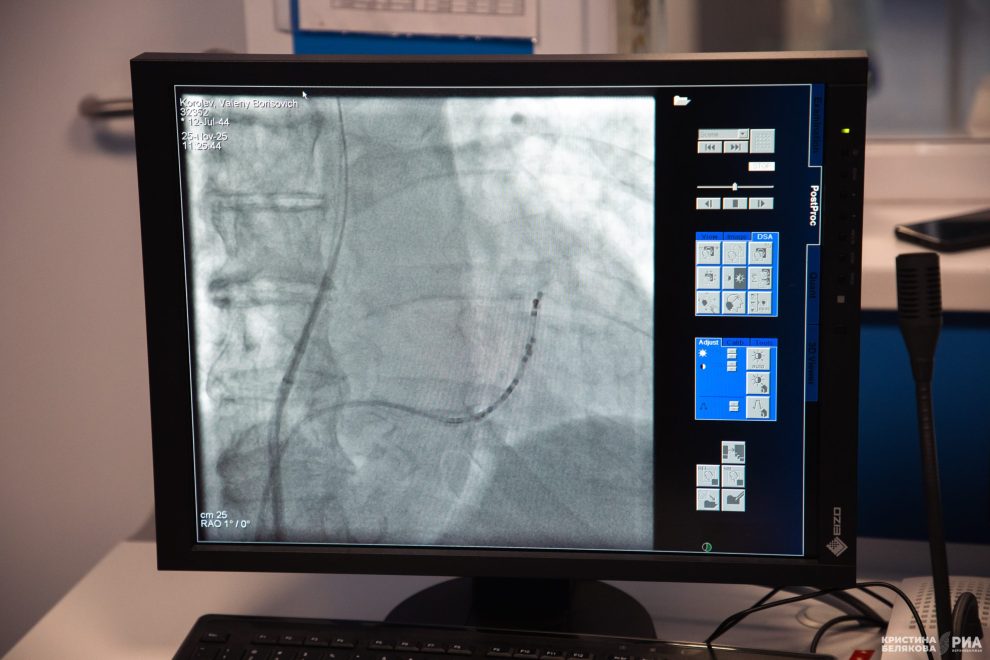

– 25 октября я поступила в больницу, – рассказывает Татьяна Николаевна. – Мне сделали два импульса, потом коронографию. Ритм сбивался снова, и врачи приняли решение о проведении криоабляции.

Преимущество этого метода заключается в том, что он позволяет без осложнений одномоментно уничтожить патологический очаг. Для пациента такая операция – не полостное вмешательство, а всего лишь прокол в области паха. Через него в сосуд вводится катетер, который подводится к сердцу. Больной при этом находится в сознании.

Как объясняет Михаил Медведь, врач по рентгенэндоваскулярным диагностике и лечению, холодовая деструкция проводится с помощью специального криобаллона, в котором нагнетается жидкий азот. Хирурги изолируют легочные вены, которые часто являются источником неправильных импульсов, вызывающих фибрилляцию предсердий. Это позволяет с меньшим количеством осложнений выполнить сложнейшую манипуляцию.